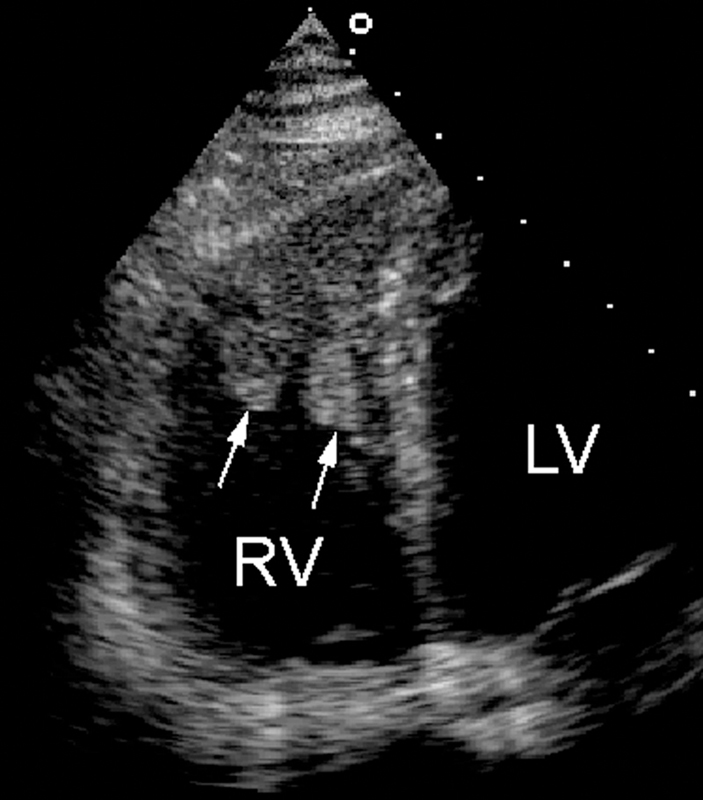

فحوصات تشخيصية لبعض امراض القلب والشرايين التاجية